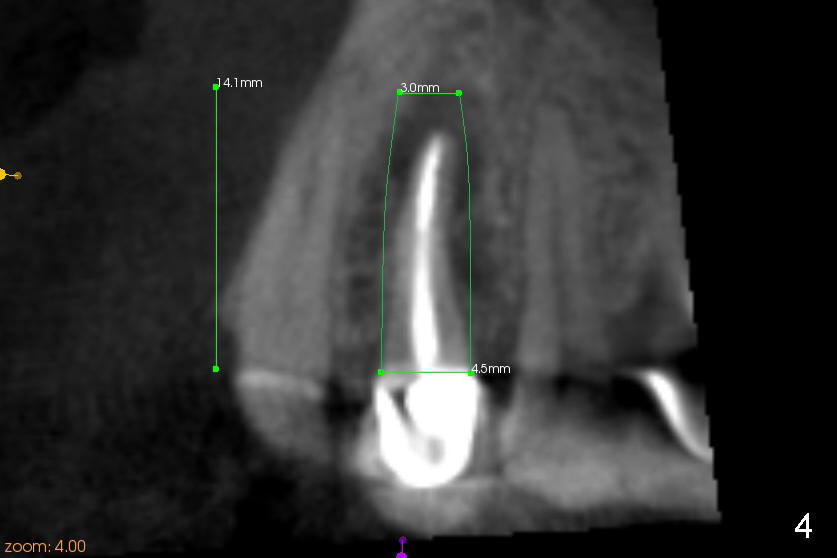

Fig.4 (sagittal section of CBCT through the upper right canine and premolar region): A 4.5x14 mm bone leveol implant is to be placed at the site of the tooth #5. The implant should achieve enough primary stability. Increase in the diameter and/or length is possible if placed properly.